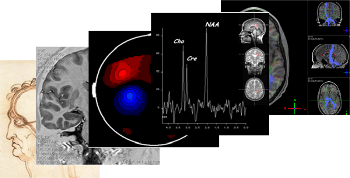

Existe uma tendência mundial para pesquisas multidisciplinares em neurociências. Uma parte considerável dessa pesquisa envolve aplicações intensivas de conceitos e métodos físicos, tais como: imagens (MRI) e espectroscopia (MRS) por ressonância magnética, MRI funcional,eletroencefalografia, magnetoencefalografia e tomografia por emissão de pósitrons, estimulação magnética transcraniana, tomografia ótica difusa no infravermelho. Esse simpósio apresentará o “state of the Field”, debaterá desafios técnicos e oportunidades de colaboração para o desenvolvimento da pesquisa do cérebro.